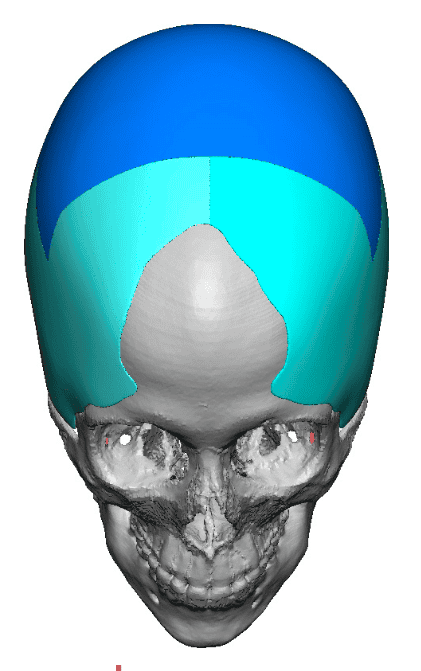

Severe narrowing skull deformity from prior sagittal craniosynostosis repair as an adult.

Complete replacement of entire skull by a custom implant with temporal fat injections.

Severe narrowing skull deformity from prior sagittal craniosynostosis repair as an adult.

Complete replacement of entire skull by a custom implant with temporal fat injections.